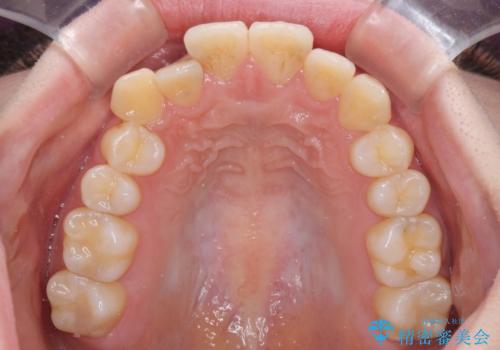

【モニター】前歯の前突感とクロスバイトをインビザラインで改善

- 前歯の突出感とクロスバイトが気になり、インビザラインによる矯正治療を希望して来院された患者様です。

上顎側切歯(上の真ん中から2番目の歯)が舌側転位している場合、インビザラインでは仕上げきれないことが多く、更には無理して動かそうとすると歯髄壊死を起こすリスクが高いと言われています。

インビザラインで歯列を移動する前に、上顎前歯をワイヤー矯正で整え、その後上下歯列をインビザラインにて矯正治療を行うこととしました。

舌側転位している側切歯特有の、切縁の位置が不揃いであったり、根元が内側に引っ込んだ状態であったりという、インビザライン独特の仕上がりになることなく、きれいに整った歯列とすることができました。